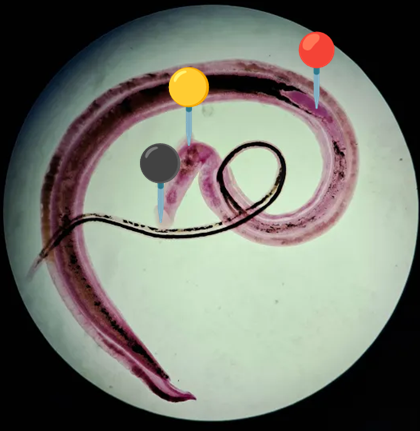

🪱🧱 Schistosoma mansoni (Cerkaria)

🧩🦠 Organelle:

⚫️ - przyssawka gębowa

🟣 - gardziel;

🟤 - jelito;

🟡 - przyssawka brzuszna;

🔴 - wyrostek ogonowy;

️⚪ - widełki.

😷❓ Parazytoza: Schistosomoza przewodu pokarmowego